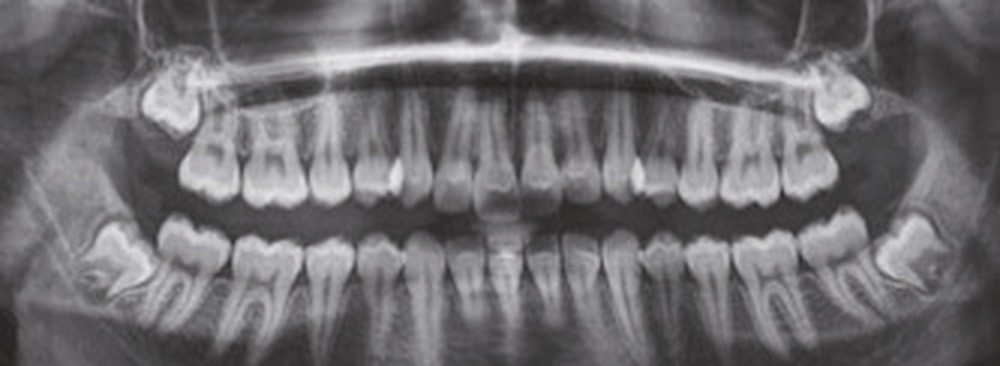

À la vue de l’examen radiographique, elle est au stade CS6 d’après la méthode de maturation vertébrale de Baccetti [1]. Elle présente une classe II squelettique de Ballard par rétrognathie mandibulaire avec un ANB de 9° et un AoBo de 9 mm sur un schéma facial normo-divergent. L’incisive mandibulaire est vestibulo-versée (IMPA = 114°). Le maxillaire est bien positionné. Elle présente de plus une dysharmonie dento-dentaire (DDD) antérieure par excès mandibulaire.

Nous équipons la patiente avec un appareil multi-attaches (.022 x .028 inch pré-informé Roth) mais nous n’avons pas activé l’arcade mandibulaire. La patiente est adressée au chirurgien maxillo-facial (Dr Gonzague Deffrennes, hôpital Beaujon) qui réalise l’avulsion des troisièmes molaires et la pose de plaques vissées avec émergence entre les premières et deuxièmes molaires mandibulaires dans l’axe des brackets (fig. 9). Étant donné l’absence d’encombrement au niveau incisif mandibulaire, nous pouvons rapidement mettre en place les tractions postérieures. Nous solidarisons ainsi le bloc antérieur de canine à canine et réalisons un recul en masse de l’arcade directement des canines aux plaques postérieures. La majeure partie du recul est faite sur un arc acier .018x.025 inch permettant le glissement. La force appliquée est de 250-300 g par côté.

Nous avons pu repositionner l’incisive mandibulaire de 8° (fig. 10), obtenir un surplomb correspondant à la classe II d’Angle et ainsi réaliser l’avancée mandibulaire. Le chirurgien accompagne celle-ci d’une génioplastie afin d’harmoniser le profil. Nous corrigeons la DDD par stripping des incisives mandibulaires ce qui permet de corriger encore de 1° l’axe incisif.